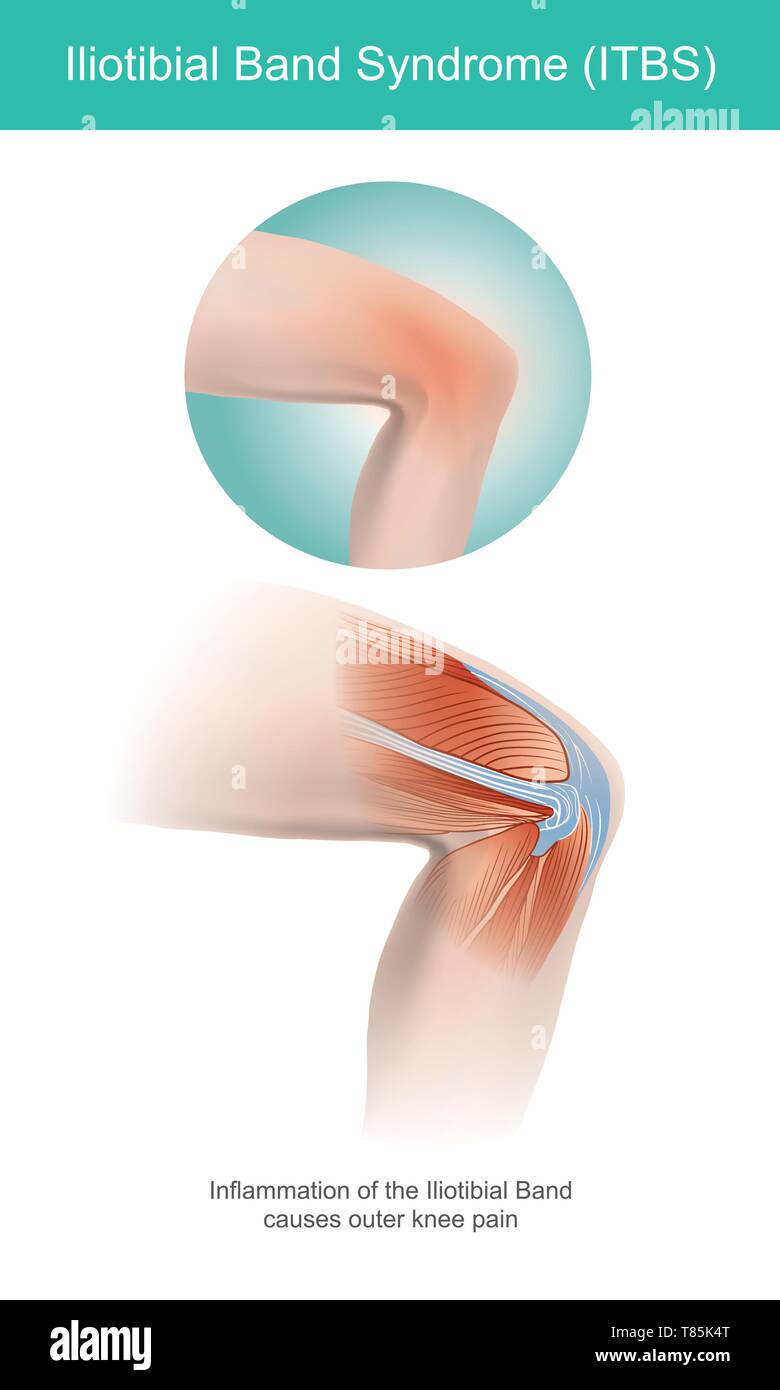

The Iliotibial Band is a longitudinal fibrous reinforcement of the fascia lata in a knee muscle. Part of anatomy human body. Illustration. Stock Vectorhttps://www.alamy.com/image-license-details/?v=1https://www.alamy.com/the-iliotibial-band-is-a-longitudinal-fibrous-reinforcement-of-the-fascia-lata-in-a-knee-muscle-part-of-anatomy-human-body-illustration-image245987192.html

The Iliotibial Band is a longitudinal fibrous reinforcement of the fascia lata in a knee muscle. Part of anatomy human body. Illustration. Stock Vectorhttps://www.alamy.com/image-license-details/?v=1https://www.alamy.com/the-iliotibial-band-is-a-longitudinal-fibrous-reinforcement-of-the-fascia-lata-in-a-knee-muscle-part-of-anatomy-human-body-illustration-image245987192.htmlRFT85K4T–The Iliotibial Band is a longitudinal fibrous reinforcement of the fascia lata in a knee muscle. Part of anatomy human body. Illustration.

The Iliotibial Band is a longitudinal fibrous reinforcement of the fascia lata in a knee muscle. Part of anatomy human body. Illustration. Stock Vectorhttps://www.alamy.com/image-license-details/?v=1https://www.alamy.com/the-iliotibial-band-is-a-longitudinal-fibrous-reinforcement-of-the-fascia-lata-in-a-knee-muscle-part-of-anatomy-human-body-illustration-image245987175.html

The Iliotibial Band is a longitudinal fibrous reinforcement of the fascia lata in a knee muscle. Part of anatomy human body. Illustration. Stock Vectorhttps://www.alamy.com/image-license-details/?v=1https://www.alamy.com/the-iliotibial-band-is-a-longitudinal-fibrous-reinforcement-of-the-fascia-lata-in-a-knee-muscle-part-of-anatomy-human-body-illustration-image245987175.htmlRFT85K47–The Iliotibial Band is a longitudinal fibrous reinforcement of the fascia lata in a knee muscle. Part of anatomy human body. Illustration.